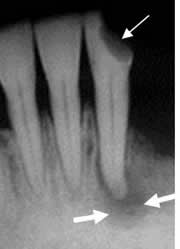

Fig 51 A. Osteomielitis.

A: TAC axial en ventana de tejidos y B: TAC en ventana ósea. Progresión de enfermedad periodontal, con destrucción ósea y prominencia de los tejidos blandos, por osteomielitis.